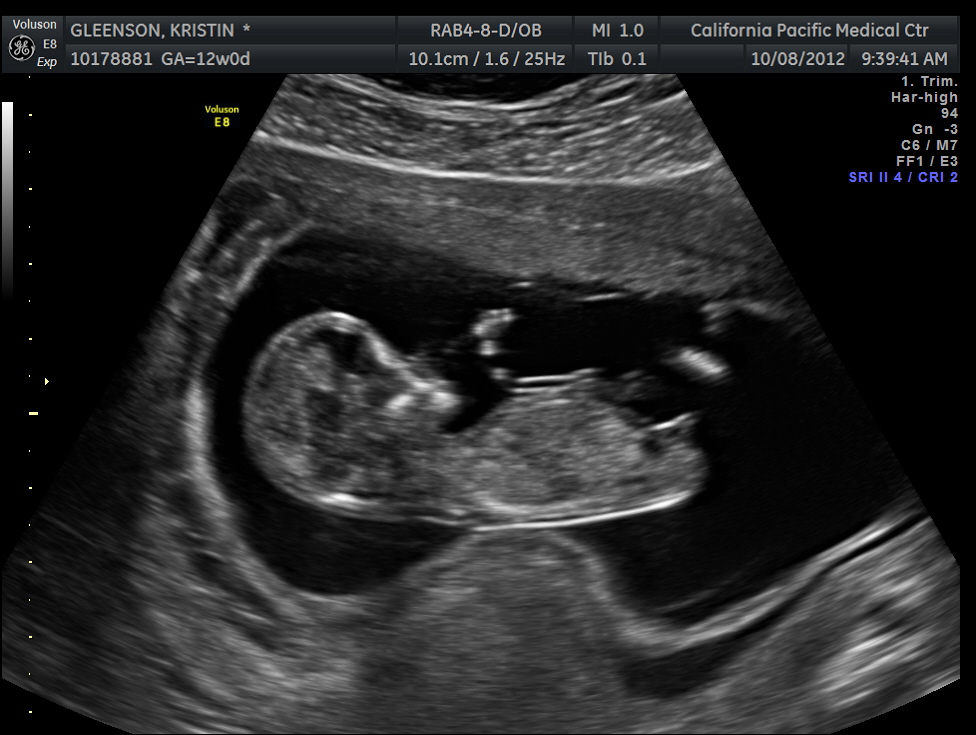

12 Week Ultrasound Boy - Boy or girl? 12 week ultrasound - Glow Community - Ultrasound of 12 weeks unborn baby boy (fetal j.snow)in there, he's fetus, not embryo anymore.

12 Week Ultrasound Boy - Boy or girl? 12 week ultrasound - Glow Community - Ultrasound of 12 weeks unborn baby boy (fetal j.snow)in there, he's fetus, not embryo anymore.. Ofcourse she added the disclaimer that it isn't 100% accurate but her explanation of. I'm so in love lol just out of curiosity what's your opinion of gender? We had 2 different techs; Do you think this is a boy or a girl? 12 weeks 5 days ultrasound/ gender reveal.

An ultrasound performed at 12 weeks is around 80 percent accurate while a scan conducted at 13 weeks may be closer to 94 percent accurate. We had our 12 week ultrasound! 12 week fist trimester screening/nuchal translucency ultrasound. 12 week ultrasound.boy or girl? 27 weeks ultrasound baby boy pheonix. Ultrasound images of your growing baby boy. Ultrasound of 12 weeks unborn baby boy (fetal j.snow) in there, he's fetus, not embryo anymore. Discover what your little boy's ultrasound will look like at different stages of pregnancy and learn some interesting facts about the making of a boy.

I know everyone says 12 weeks is too soon to tell the i've had a lot of fun looking at skull theory! Ultrasound proves boy at 12 weeks! We're expecting twins and based on that i reckon we have a boy and a girl, but obviously it's mostly old. Ultrasound of 12 weeks and 4 days unborn baby boy. Of my 3 pregnancies, the ultrasound tech only offered me a guess at 12 weeks once, and it was because she did your baby end up being a boy? Is she spot on or should we wait until around 20 weeks to make sure? Our ultrasound technician told us it looks like a boy but. 00:42 12 week 1 day to be exact. 12 weeks is generally too early. Baby boy staton's 12 week checkup! I wasn't expecting to learn the gender this early, but the perinatologist is 95% sure it's. Missed miscarriage 12 week ultrasound. I'm 12 weeks pregnant and yesterday i went for a nuchal screening ultrasound (testing for birth defects, etc).